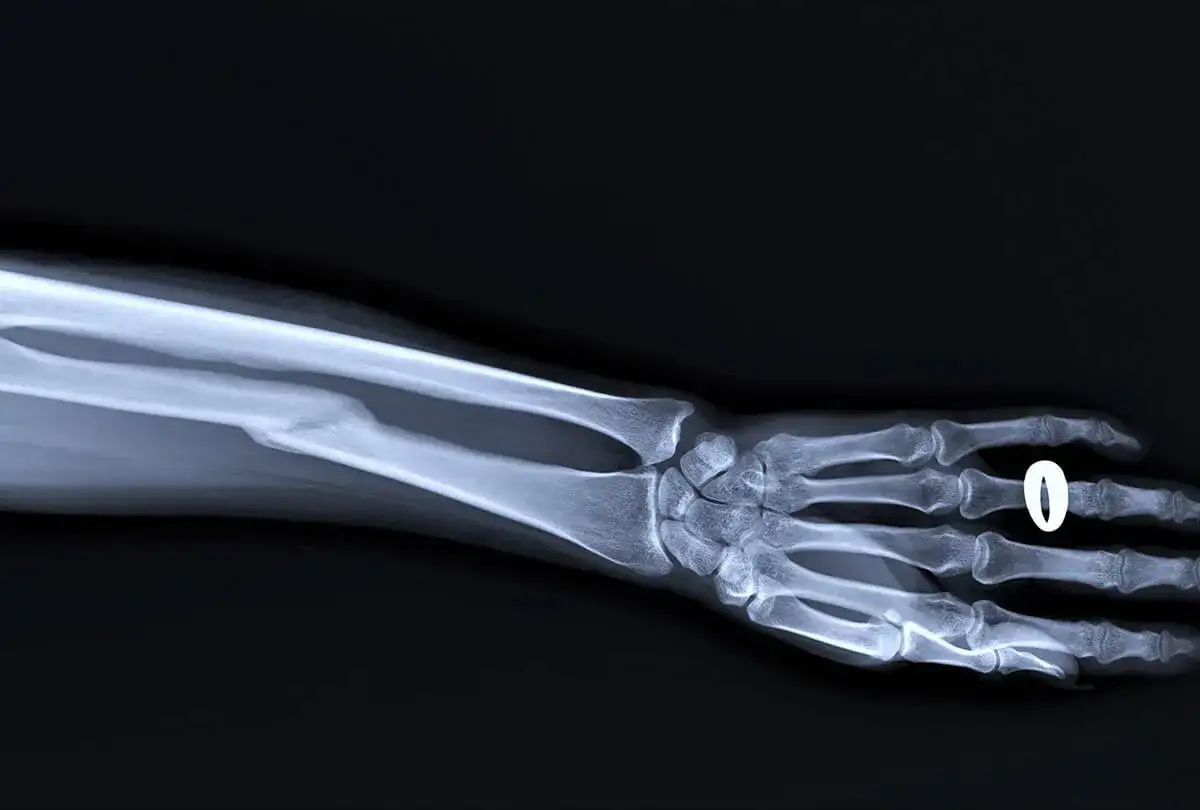

Dowiedz się krok po kroku, jak uzyskać odszkodowanie z PZU za złamanie nasady dalszej kości promieniowej. Sprawdź potrzebne dokumenty i terminy.